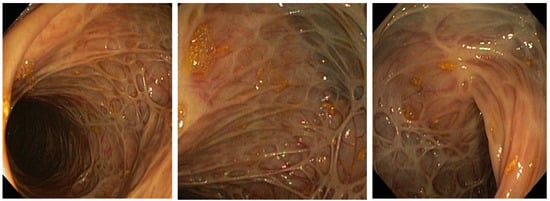

Figure 2. Colon mucosa appearance on colonoscopy performed in December 2018. Note the absence of active Crohn’s disease.

During steroid tapering, at the dose of 35 mg prednisolone, patient had increased number of bowel movements to four–five liquid stools daily followed by increase in CRP levels (141 mg/L) and hemolytic crisis. After detailed workup from an immunologist and hematologist, AIHA was considered as an EIM of CD. In addition, the previous PTE was now considered provoked, since tests for inherited and acquired thrombophilia were negative. Due to steroid-dependent form of disease, we initiated treatment with infliximab in combination with azathioprine. The patient responded to first infliximab infusion, CRP levels decreased (23 mg/L), and she had two formed stools. The patient was discharged and the second induction dose administered after 2 weeks was uneventful. At the third induction dose, on week 6, CD was in clinical remission, with two formed stools daily, no fever, and no abdominal pain, but laboratory signs of another hemolytic crisis were observed with severe anemia (Hgb 60 g/L). We decided to increase the corticosteroid dose to 40 mg prednisolone and blood was taken to determine infliximab trough level and antibodies. Infliximab trough levels were low (0.73 mg/mL) with negative antibodies, so we optimized the treatment regimen by shortening the interval to 4 weeks. The patient responded well, steroids were weaned, and the patient was in clinical and laboratory remission from February 2017 until July 2019. A control colonoscopy in December 2018 confirmed endoscopic remission and low histological activity, as seen in Figure 2. In July 2019, the patient experienced a relapse of CD with abdominal pain and up to 10 liquid bloody stools daily. Infliximab trough levels were low (0.5 mcg/mL) with elevated antibodies (46 IU/mL). The patient was admitted to the Clinic for gastroenterology and hepatology, University Clinical center of Serbia, and started on steroids. The biologic drug was changed within class to adalimumab, as the patient was stable on the first anti-TNF for more than 2 years. Unfortunately, this resulted in a merely partial clinical response with no clinical remission. In October 2019, a colonoscopy revealed severely active disease from the rectum to hepatic flexure, and the biological drug was changed from one of the anti-TNF class to vedolizumab. The patient has since been in clinical, laboratory and endoscopic remission with no more flairs of AIHA. The colonoscopy performed in November 2020 showed endoscopic remission of the disease. Pathohistology confirmed remission with only focal inflammation of low activity. The patient got pregnant, and the pregnancy was uneventful. In July 2021, an elective Caesarian section was performed, and she delivered a male baby (birth weight 4400 g, APGAR score 9). Vedolizumab therapy is ongoing, and the patient is still in remission.